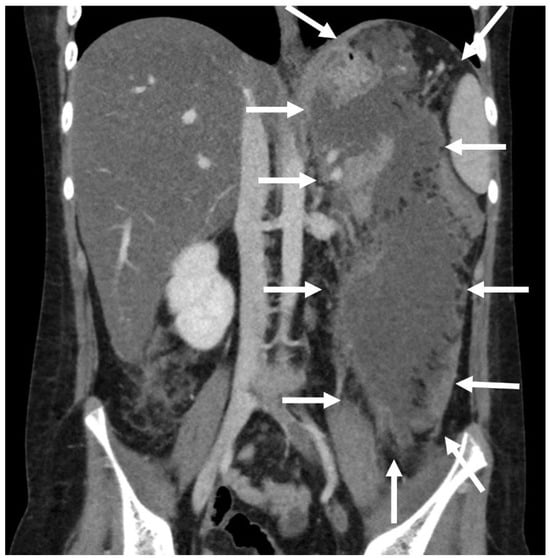

Figure 6.

Patient n°3 MRI. Reduction of the walled-off necrosis; the device is in place (in the white circle).

A 10-year boy affected by T-lymphoblastic lymphoma developed a WON after chemotherapy-induced necrotic-hemorrhagic pancreatitis, with fever, vomit and abdominal pain. Clinical conditions were also complicated by deep vein thrombosis involving the left femoral vein and inferior vena cava. Abdominal CT showed a large WON, with a major diameter more than 22 cm (Figure 5). Considering the worsening of clinical condition and the need to an early resume of the chemotherapy, he underwent a primary EUS-guided cystogastrostomy and EC-LAMS positioning; we did not perform necrosectomy. Post-operative course was uneventful. MRI performed 37 days after the procedure, showed a significant reduction of the WON (Figure 6); subsequent US images were performed for follow-up, until the WON was no more visible. Endoscopic removal of the device was performed 48 days after cystogastrostomy.